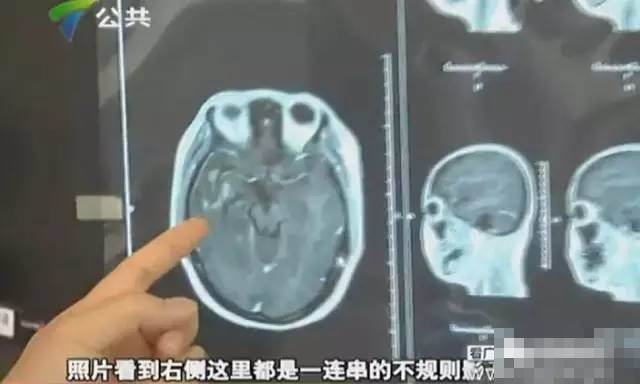

這個孩子也是經常吃不熟的食物,腦部被寄生蟲「啃」出一個洞▼